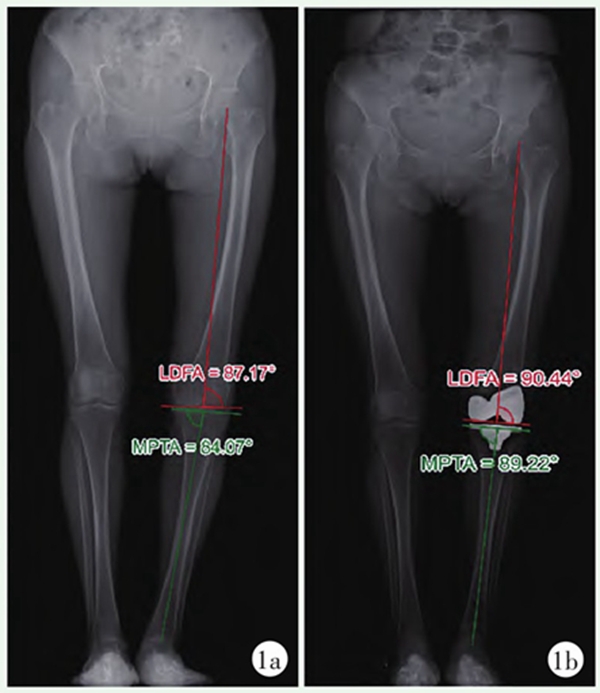

图1 MA-TKA患者双下肢站立位全长X线片

1a:术前X线片;1b:术后X线片患者股骨及胫骨排列被矫正至90°中立位;LDFA:股骨远端外侧角;MPTA:胫骨近端内侧角